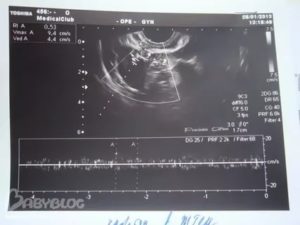

– На 12 день цикла у меня обнаружили доминантный фолликул 23 мм. А на 23 день – желтое тело 12 мм с кровотоком. Я беременна?

– УЗИ показывает, что была овуляция. Есть ли беременность, говорить пока рано. Но в этом цикле она возможна, ведь овуляция была. Сдайте кровь на ХГЧ.